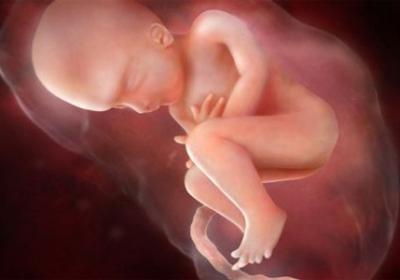

Что может быть лучше, чем рождение еще одной жизни? Особенно остро это ощущение для будущей мамы в период второго триместра беременности и в частности – на 24 неделе.